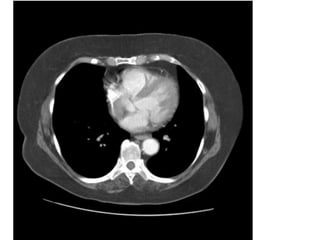

Figure 9. PE ở bn nữ 42 tuổi, đau ngực và khó thở nhiều.

- Hình ảnh thất phải dãn lớn hơn thất trái.